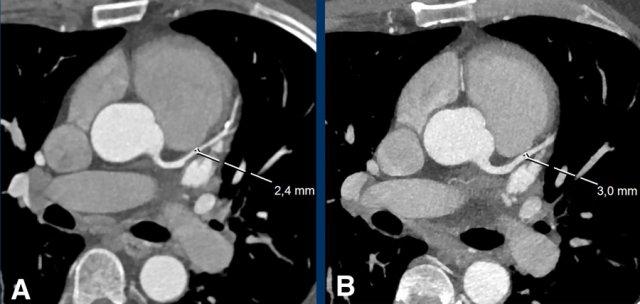

Spotty calcification

Spotty calcifications are usually defined as calcifications < 3

mm.

Small spotty calcifications on CTA are associated with high-risk plaques (12).